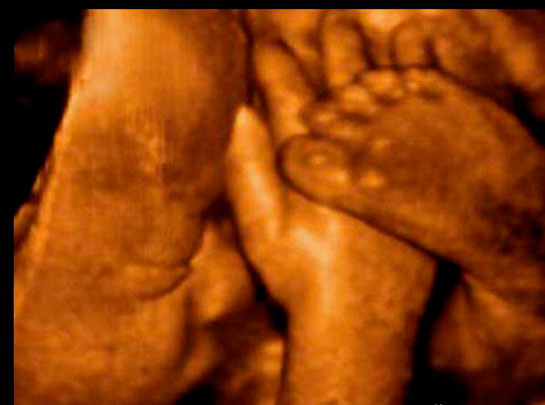

30 haftalık gebelik, hamileliğin üçüncü trimesterinin başlangıcını işaret eder ve bu dönemde hem anne hem de bebek için önemli değişimler ve gelişmeler yaşanmaktadır. Gebelik süreci, fetal gelişim, anne sağlığı ve doğum süreci açısından kritik bir zaman dilimidir. Bu makalede, 30 haftalık gebelik döneminin fiziksel, duygusal ve sağlık açısından önemli yönleri ele alınacaktır. Fetal Gelişim30. haftada, fetüs büyük ölçüde gelişimini tamamlamış durumdadır. Bu dönemde fetüsün büyüklüğü ve gelişimi aşağıdaki gibi özetlenebilir: